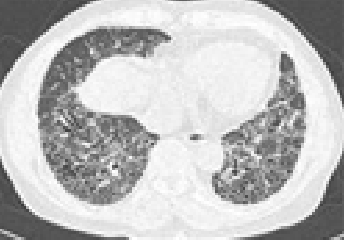

석면폐증(잠복기 약 15~40년)

잠복기가 약 15~40년에 걸친 석면으로 인한 석면폐증에 대한 CT사진

석면에 의한 폐 조직에 상처로 나타나는 폐섬유화 증상

• 폐의 섬유화로 희게 나타나며 공기집이 생겨 벌집모양으로 나타남

석면폐증의 병 유형(의심형, 초기형, 진행형) 및 폐기능 장해단계(정상, 경도장해, 고도장해)에 따라 1~3급으로 구분

• 석면폐증의 병 유형 : 폐섬유화 소견에 따라 의심형, 초기형, 진행형으로 구분

폐섬유화 소견에 따른 의심형 이미지 〈의심형〉

폐섬유화 소견에 따른 초기형 이미지 〈초기형〉

폐섬유화 소견에 따른 진행형 이미지 〈진행형〉